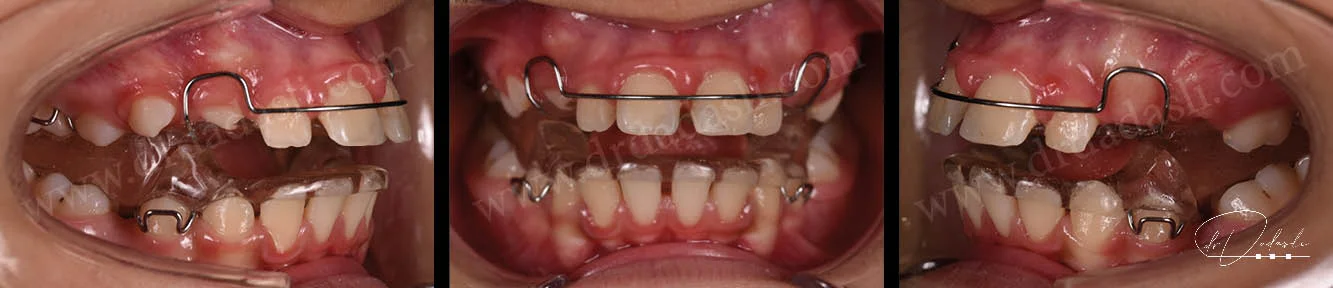

Hareketli ortodontik apareyler – genellikle çocuklara uygulanmaktadır. Henüz gelişim çağında olan çocuklarda hareketli apareylerle birçok iskeletsel ve dişsel problemler çözülebilir (Şekil 16 ve Şekil 17). Erken yaşta çözülebilecek problemler arasında çapraz kapanış, alt çene geriliği, üst çene geriliği, alt çenenin önde olması, üst dişlerin önde olması, uzun süre parmak emmeye bağlı olarak gelişen problemler, çeşitli kötü alışkanlıklar sonucu oluşan diş ve çene problemleri vs gibi problemlerdir. Özellikle bazı problemleri erken yaşta teşhis edip, tedavisinin yapılması gerekmektedir. Çocuk büyüme gelişimini tamamladıktan sonra iskeletsel problemleri çözümü genellikle cerrahi yolla olmaktadır. Bu yüzden çocuğunuz 7 yaşındayken ortodonti uzmanına başvurmanız gerekmektedir. Erken yaşta teşhis edilen problemler çoğunlukla kolayca çözülebilmektedir.